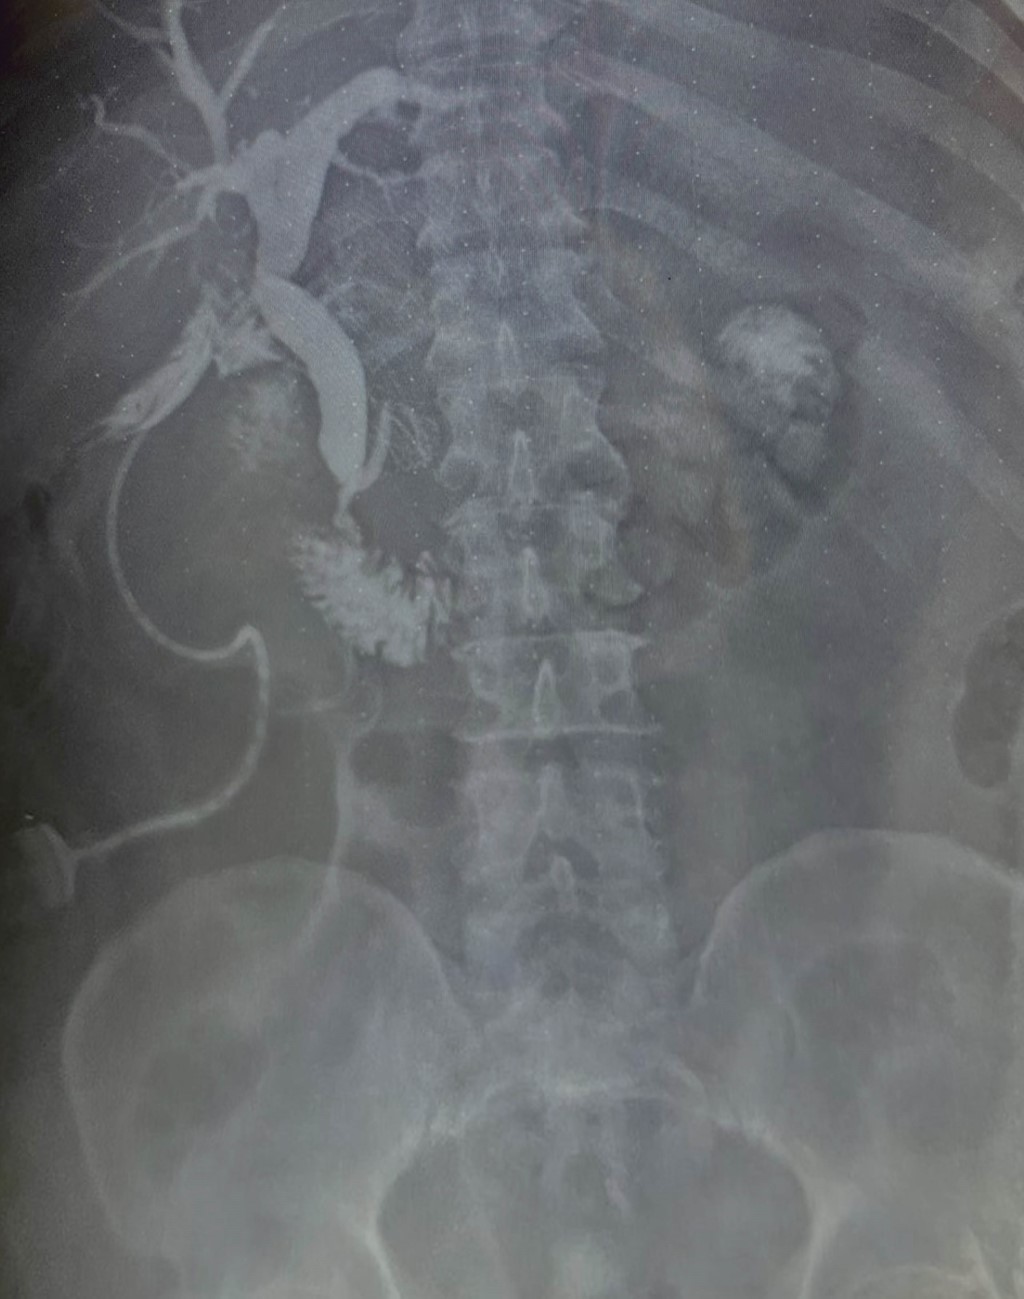

A 64-year-old male began his illness with jaundice and denied other symptoms. It is noteworthy that he had it for at least three days before he arrived at the emergency room; his physical examination was without alterations, and his lab tests showed total bilirubin of 25 mg/dl, direct bilirubin of 22 mg/dl, alkaline phosphatase 235 IU/l, gamma-glutamyl transferase 157 IU/l, creatinine 2.5 mg/dl, and the rest of the test were within normal limits. An abdominal ultrasound was performed, which reported an ill-defined gallbladder and dilatation of the biliary tract of 19 mm (Figure 1); a 12 mm bile duct stone was observed in the common bile duct. The diagnosis of choledocholithiasis was done. Tumor markers were requested, with a report of CA 19-9 > 8,000 IU; cholangioresonance was performed, which showed bile duct dilatation (bile duct) of 20 mm and a 16 mm stone at the level of the ampulla. No morphology of the gallbladder (GBV) was reported. The patient was a candidate for endoscopic retrograde cholangiopancreatography (ERCP), according to the Gastroenterology service. ERCP was performed without being able to extract the lithium, and the patient was scheduled for cholecystectomy with an exploration of the biliary tract; the transoperative examination revealed biliperitoneum, lysis of the GB, a cholecystocoledochobiliary fistula (Figure 2) and a single 15 mm stone; a T probe was placed. Since there was no hepatopancreaticobiliary surgeon a definitive repair was not performed. A transoperative cholangiography revealed passage of contrast material to the duodenum without apparent leakage through the fistulous orifice (Figure 3). The patient had a favorable postoperative evolution; the drainage through a T catheter was an average of 500 ml per day with progressive decrease, with the improvement of hyperazoemia and a urinary flow greater than 0.5 ml/kg/h. A postoperative cholangiography showed no leaks with the passage of the contrast medium to the duodenum. The pathology report revealed a moderately differentiated adenocarcinoma of the gallbladder with muscular infiltration (Figure 4). The patient refused medical treatment and decided to voluntary discharge; he understood and accepted the risks and was lost for follow-up.

In general, preoperative diagnosis is difficult; it is usually suspected in older patients with right hypochondrium pain and atypical symptoms. Ultrasound is not very sensitive in detecting findings, as it has accuracy as low as 11% in some reported series. Some authors mention suggestive data for MS: atrophic GB, dilatation of the HD with normal caliber of the GBCD (92%). Other indirect data are dilatation of the GBCD greater than 7 millimeters, with or without a stone greater than 10 mm in CBV, pneumobilia, and Hartmann's stone.7

In the case of GBCA, calcifications, luminal invasion, loss of the liver-vesicle interface, direct hepatic infiltration, irregular wall, and vesicular polyps larger than 10 mm are the known findings.3 Ultrasound is not helpful to assess the stage, i.e., the extent of the disease.

Figure 1